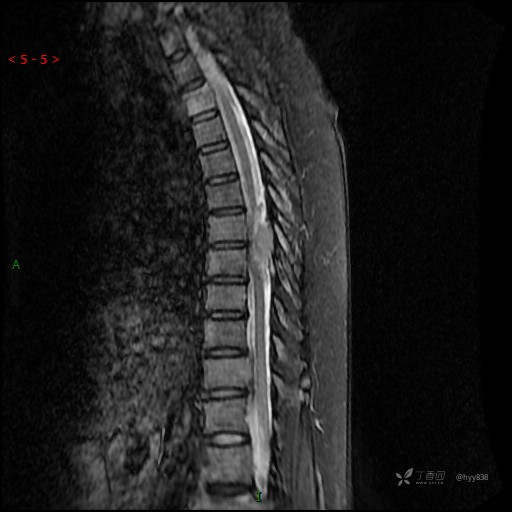

MRI SAG T2WI+T1WI